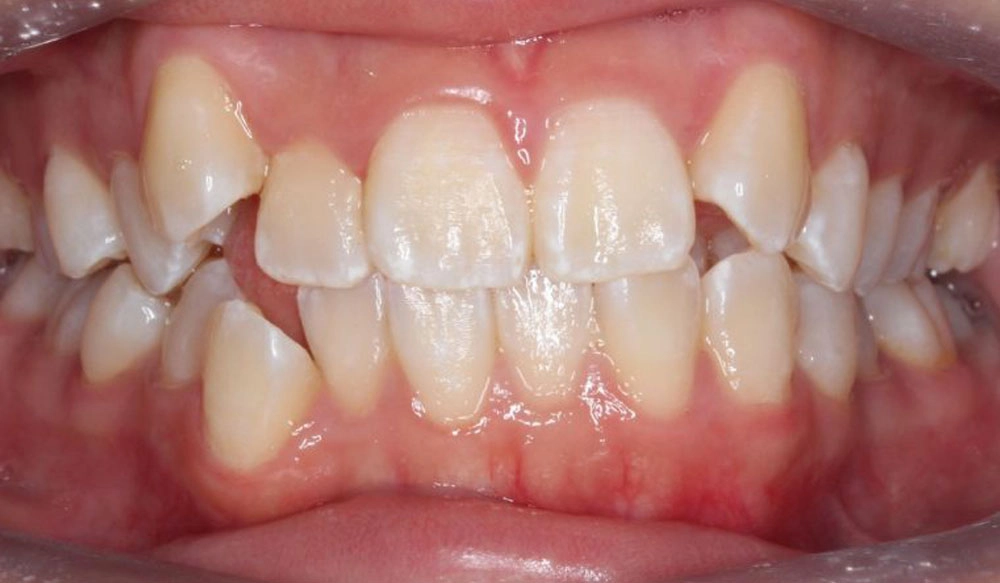

Cắn sâu

Cắn sâu là tình trạng mà sự phủ theo chiều dọc của các răng cửa ở khớp cắn trung tâm lớn hơn 30 – 40%.

Thông tin bệnh nhân:

Tuổi: 13

Giới tính: Nam

Lựa chọn điều trị Invisalign: Invisalign Comprehensive

Tổng thời gian điều trị:

24 tháng